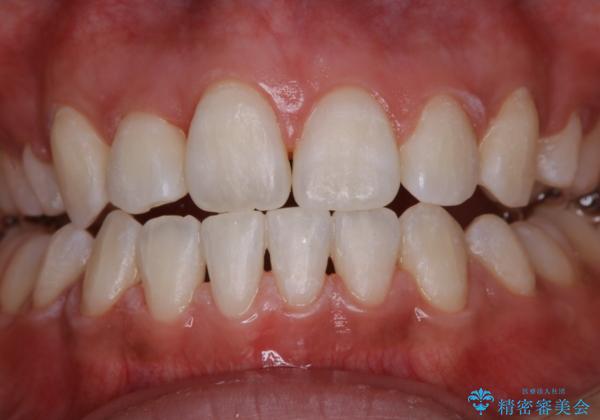

ホワイトニング 1日で真っ白な歯に

- ホワイトニングで歯を白くしたいとのことでした。

処置前クリーニング¥3300・オフィスホワイトニングのエクセレントコース¥29700を行いました。

- ¥33000費用は治療当時の料金となります